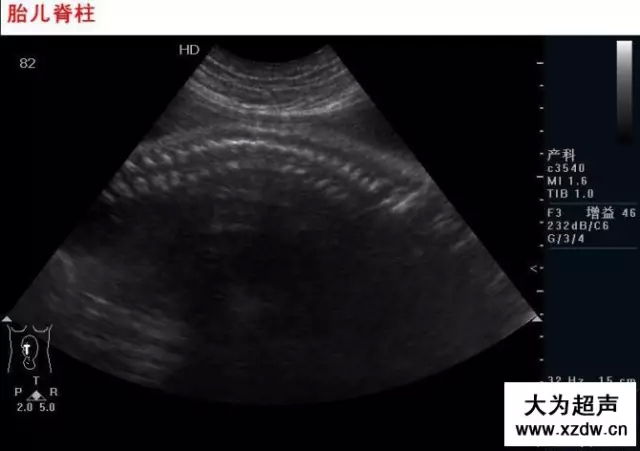

產科超聲正常圖片